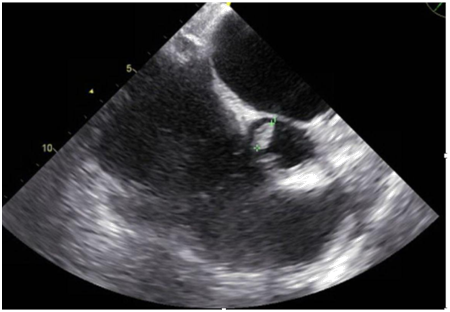

A 47-year-old immunocompetent male with a medical history significant for active intravenous heroin abuse presented to the hospital with fever and respiratory distress. On admission, he was diaphoretic, febrile, and hypoxemic with an oxygen saturation of 70% on ambient air, necessitating intubation and mechanical ventilation. Chest radiography revealed a right lower lobe infiltrate concerning for pneumonia, blood cultures were obtained, and vancomycin and piperacillin-tazobactam were empirically administered. Within 48hours, blood cultures grew Candida tropicalis, and antifungal therapy with micafungin was initiated. Computed tomographic scan of the chest revealed bilateral upper lobe infiltrates and dense consolidations with air bronchograms in the bilateral posterior lobes. Transthoracic echocardiography demonstrated severe aortic thickening and aortic regurgitation but no clear evidence of vegetation despite clinical suspicion for endocarditis. Sites of metastatic infection, including endophthalmitis and septic emboli to the brain were ruled out, and antifungal therapy was adjusted to amphotericin B and flucytosine. A subsequent transesophageal echocardiogram revealed a 1.3cm aortic valve vegetation associated with severe aortic regurgitation, for which he underwent aortic valve replacement with a bioprosthetic pericardial valve. Intra-operative cultures from the aortic valve confirmed Candida Tropicalis. He was discharged to a skilled nursing facility to complete 6weeks of antifungal therapy.

Figure 2 Transesophageal Echocardiogram showing left atrium dilatation (4.8cm); and severe aortic valve regurgitation.